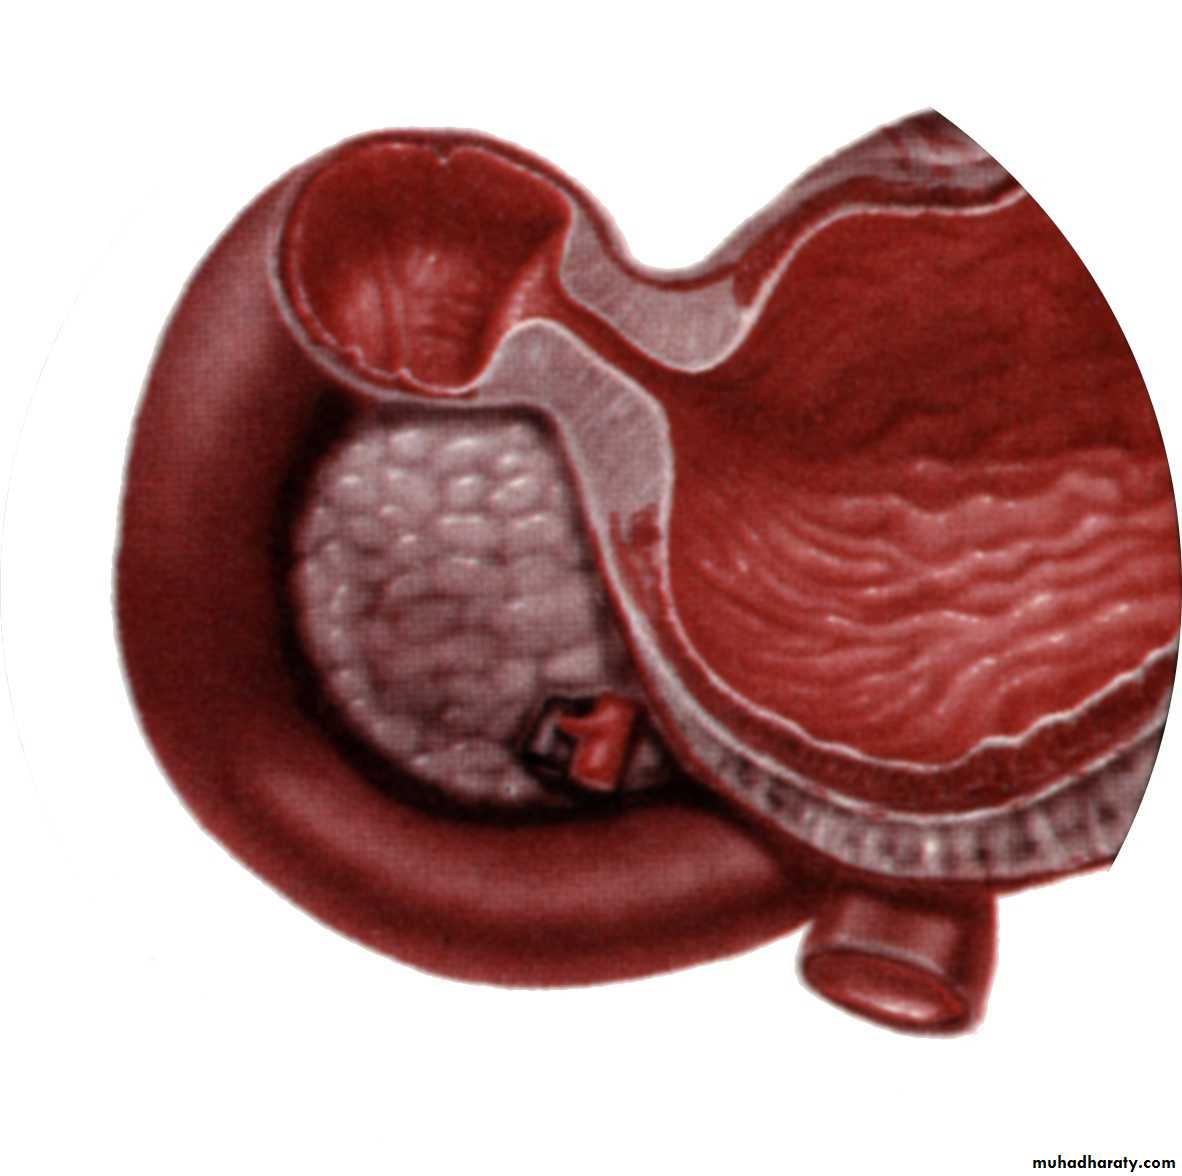

☆ Acquired condition☆Hypertrophy of circular muscles of the pylorus☆ Incidence 1-4 in every 1000 live birth☆ Boys are affected four times more than girls☆ Aetiology is multifactorial☆ Age of presentation is 2-8 weeks of life☆ Rare after 3 month of age

Pyloromyotomy